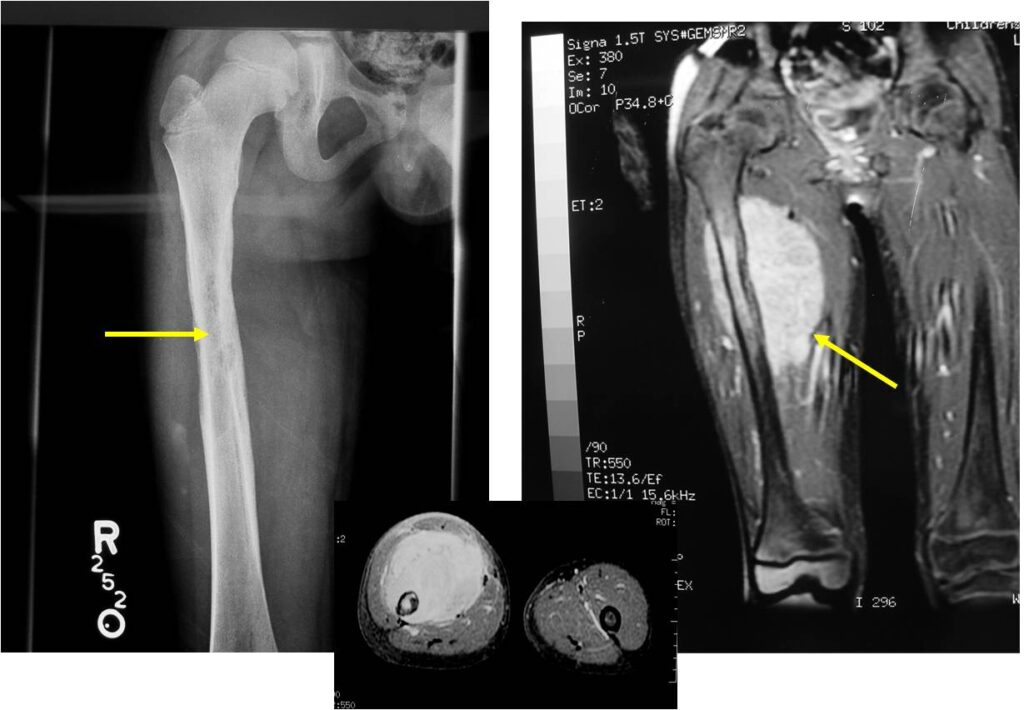

- Soft Tissue Mass in 90% of of cases

- Most protocols administer preoperative chemotherapy then surgery is performed. Surgery is followed by several courses of postoperative chemotherapy.

- Ewing sarcoma responds well to chemotherapy. Often there is a dramatic reduction in size of the tumor.

- Lesions grossly confined to bone have a better prognosis than those with a soft tissue component

- Response to preoperative chemotherapy: Greater than 90% tumor necrosis (Good response) correlates with a better prognosis

- Tumors greater than 8cm in maximum dimension and those with greater than a volume of 100cc have been associated with a worse prognosis